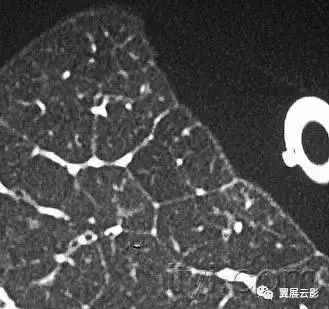

三十九、马赛克征

CT:本征象表现为不同的密度成片状镶嵌,可为间质性病变、闭塞性小气道病变(图)或者血管阻塞性疾病。马赛克征比马赛克样少血或者低灌注具有更强的诊断含义。由于支气管或细支气管阻塞导致的空气滞留可以导致局部的密度减低,在呼气相CT上表现更加明显。

该征象也可以见于间质性肺部疾病,特征是磨玻璃影,此时高密度代表间质性病变,低密度代表正常的肺。